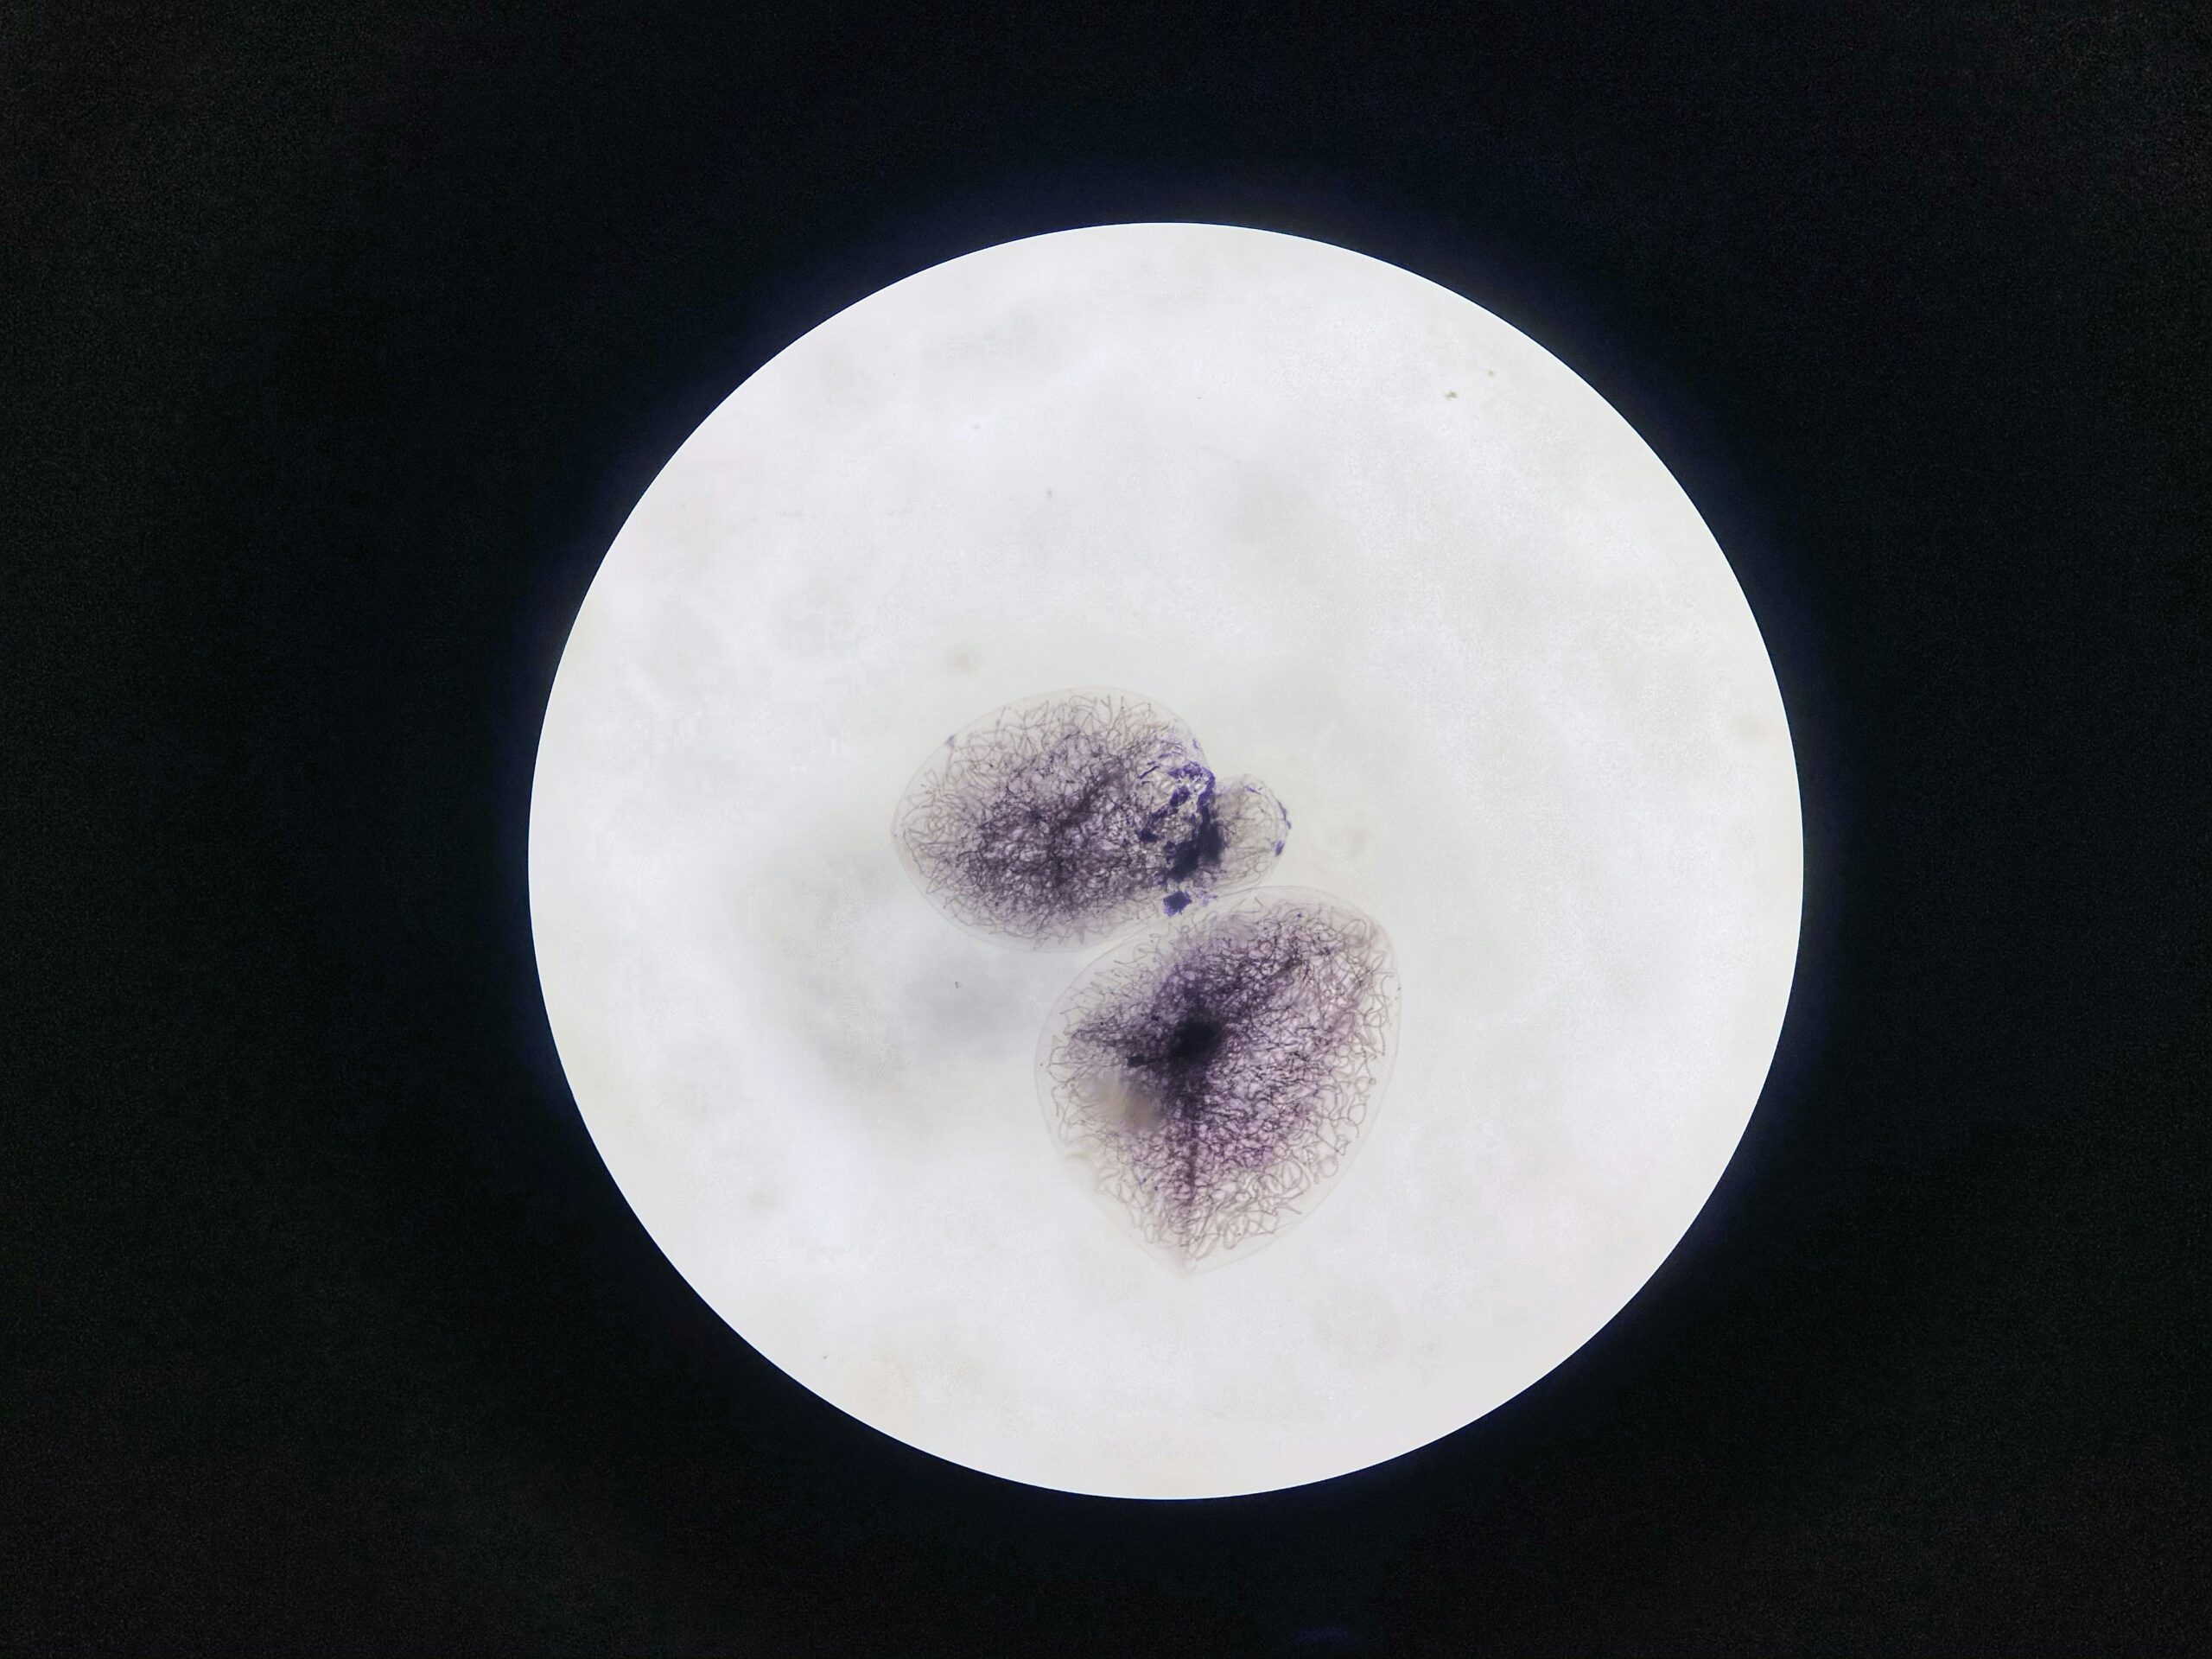

En IREGCI nace el primer bebé en República Dominicana mediante la técnica PGD

El Instituto de Reproducción y Ginecología del Cibao (IREGCI) se complace en anunciar al país